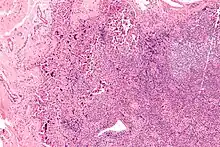

| Lymphadenopathy due to systemic lupus erythematosus with characteristic necrosis and haematoxylin bodies. H&E stain. | |